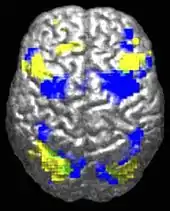

The underconnectivity theory of autism posits that autistic people tend to have fewer high-level neural connections and less global synchronization, along with an excess of low-level processes.[27] Functional connectivity studies have found both hypo- and hyperconnectivity in brains of autistic people.[28] Hypoconnectivity is commonly observed for interhemispheric and cortico-cortical functional connectivity.[29] Some studies have found local overconnectivity in the cerebral cortex and weak functional connections between the frontal lobe and the rest of the cortex.[30] Abnormal default mode network (task-negative) connectivity is often observed. Toggling between task-negative network activation and task-positive network activation (consisting of the dorsal attention network and salience network) may be less efficient, possibly reflecting a disturbance of self-referential thought.[31] Such patterns of low function and aberrant activation in the brain may depend on whether the brain is performing social or nonsocial tasks.[32]